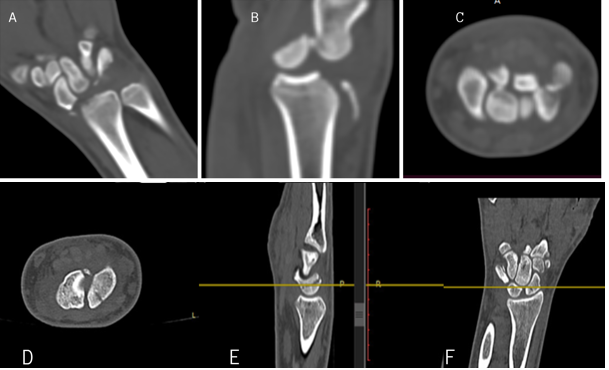

On examination, there was tenderness in the anatomical snuff box on both sides, and the scaphoid compression test was positive bilaterally. There was a significant restriction in the movements of both wrists. He was evaluated with X-rays (Fig. 1) and CT (Fig. 2) of the bilateral wrist and was diagnosed as a case of bilateral closed scaphoid fracture (Herbert type B4 on the left side and type B2 on the right side) with transcaphoid, trans-triquetrum perilunate dislocation on the left side and coronoid fracture (Regan-Moorey II) on the left side (Fig. 3). Closed reduction of perilunate dislocation was done in an emergency under local anesthesia, and a bilateral glass holding slab was applied for scaphoid fracture. While the patient had no prior comorbidities, bone health markers such as serum calcium and Vitamin D levels were evaluated and found to be within the normal range. The patient had no history of smoking or alcohol consumption. These may be important determinants of healing, particularly in older or systemically compromised individuals.

Figure 2: Computed tomography (CT) of left wrist showing scaphoid fracture in coronal (a), sagittal (b), and axial (c) sections. CT of right wrist showing scaphoid fracture in axial (d), sagittal (e), and coronal (f) sections.

Figure 3: Computed tomography left elbow showing Regan-Moorey II coronoid process fracture in axial (a), coronal (b), and sagittal (c) section.